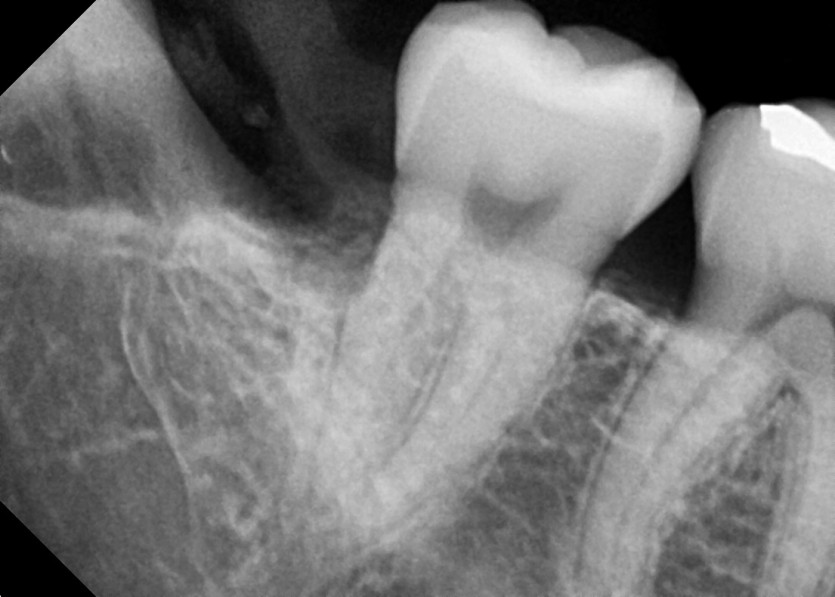

#48 사랑니 발치

구강 외과 전문의가 당일 발치했습니다.